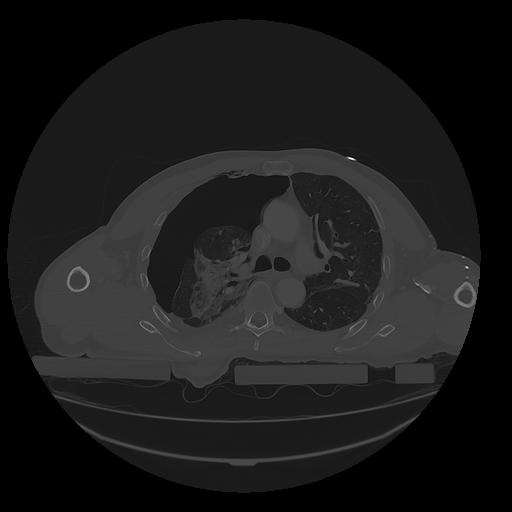

31 PULMON,CE,Vol,1.0,PULMON,,